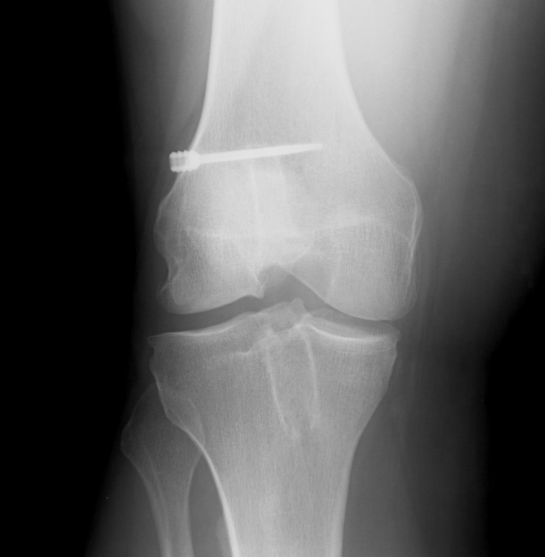

2. X-ray assessment

Lateral x-ray

Femoral tunnel

- intersection of line posterior femoral cortex and Blumensaat's line

Tibial tunnel

- posterior to Blumensaat's line in full extension

- parallel to Blumensaat's line

Pinczewski JBJS Br 2008

- 200 patients followed up over 7 years

1. Posterior femoral tunnel placement

- 86% along Blumensaat's line

2. Anterior tibia tunnel placement

- 48% along tibial plateau

- parallel to Blumensaat's

AP Xray

1. Medial tibial tunnel placement

- 46% (towards medial)

2. Lateral femoral tunnel placement

- 42% from lateral LFC

3. Graft inclination

- 19o

11% rupture rate over 7 years

- associated with posterior tibial tunnel placement

Good rotational stability

- 19o inclination in coronal plane

- avoid too vertical orientation